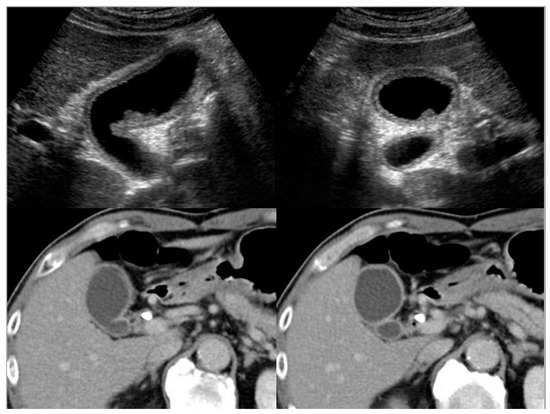

4.1. Diffuse Type of IgG4-CC

4.2. Localized Type of IgG4-CC